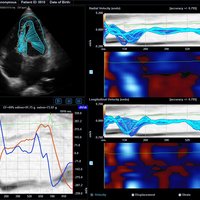

• M-Modus, Auto IMT, CV Measurement and Report, EKG, Cube Strain, Stressecho, Tissue Doppler Imaging (Kardiologie)